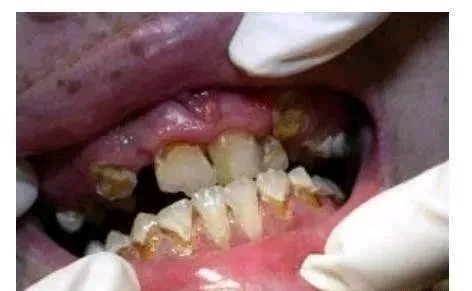

吸冰毒成瘾者的牙齿很黑,着色和腐蚀严重,这种牙是没有办法治疗的。

毒品可对口腔粘膜和牙齿造成多重损害,毒品直接刺激上呼吸道粘膜形成粘膜的溃疡,造成口腔内菌群失调,出现牙龈出血等严重的炎症,进而牙龈萎缩、牙齿松动,严重影响咀嚼功能。

吸毒刺激口腔黏膜上皮细胞异常增生,导致黏膜角质角质层逐渐增厚,对骨骼系统、免疫系统都造成危害,导致牙周病发生几率特别高,增加口腔感染的风险,长期刺激口腔黏膜还会增加罹患口腔癌的机会。

吸毒也会造成口气重,影响交际,造成牙根暴露、牙齿松动等慢性炎症,抑制免疫功能!

牙周病—冰毒成瘾者通常不会定期做口腔检查,口腔保健的缺乏会引发牙周病。同时,牙齿和牙龈都需要血液来保持健康,冰毒使口腔组织的血管收缩,血流量减少,最终导致口腔组织坏死。

冰毒牙的第二阶段:嘴唇上出现伤口,牙龈开始退缩,龋齿呈严重趋势

冰毒牙的第三阶段:龋齿发展到牙龈边缘以下,牙齿出现缺失,嘴唇的伤口越发明显